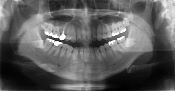

当院は、来院していただいた患者様全員にお口全体の写真(パノラマ)というものを

撮らせていただいております。

まず、口全体の写真(パノラマ)には、歯・顎の骨・銀歯やインプラント・虫歯・歯周病の状態が映し出されます。